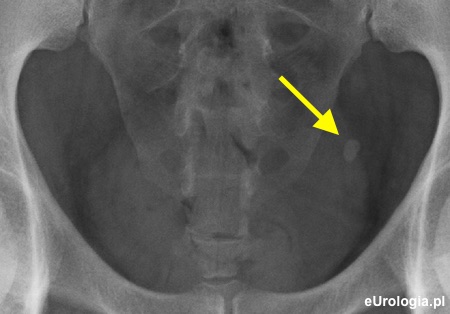

Zdjęcie przeglądowe jamy brzusznej. Widoczny cień wapienny w miednicy małej po stronie lewej o wymiarach 10x7 milimetrów

Zółtą strzałką zaznaczono złóg w lewym moczowodzie o wymiarach 8,7x4,7 milimetra.